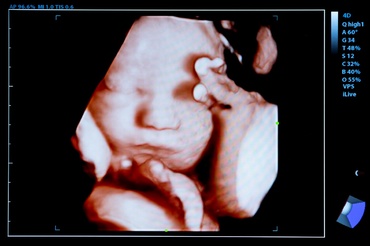

Aproape 50% dintre femei ezită să vorbească cu medicul despre problemele legate de sarcină

Conform unui sondaj unde au participat 2.400 de mame, aproape jumătate dintre ele (44,7%) au spus că au ezitat să vorbească cu medicul despre problemele legate de...